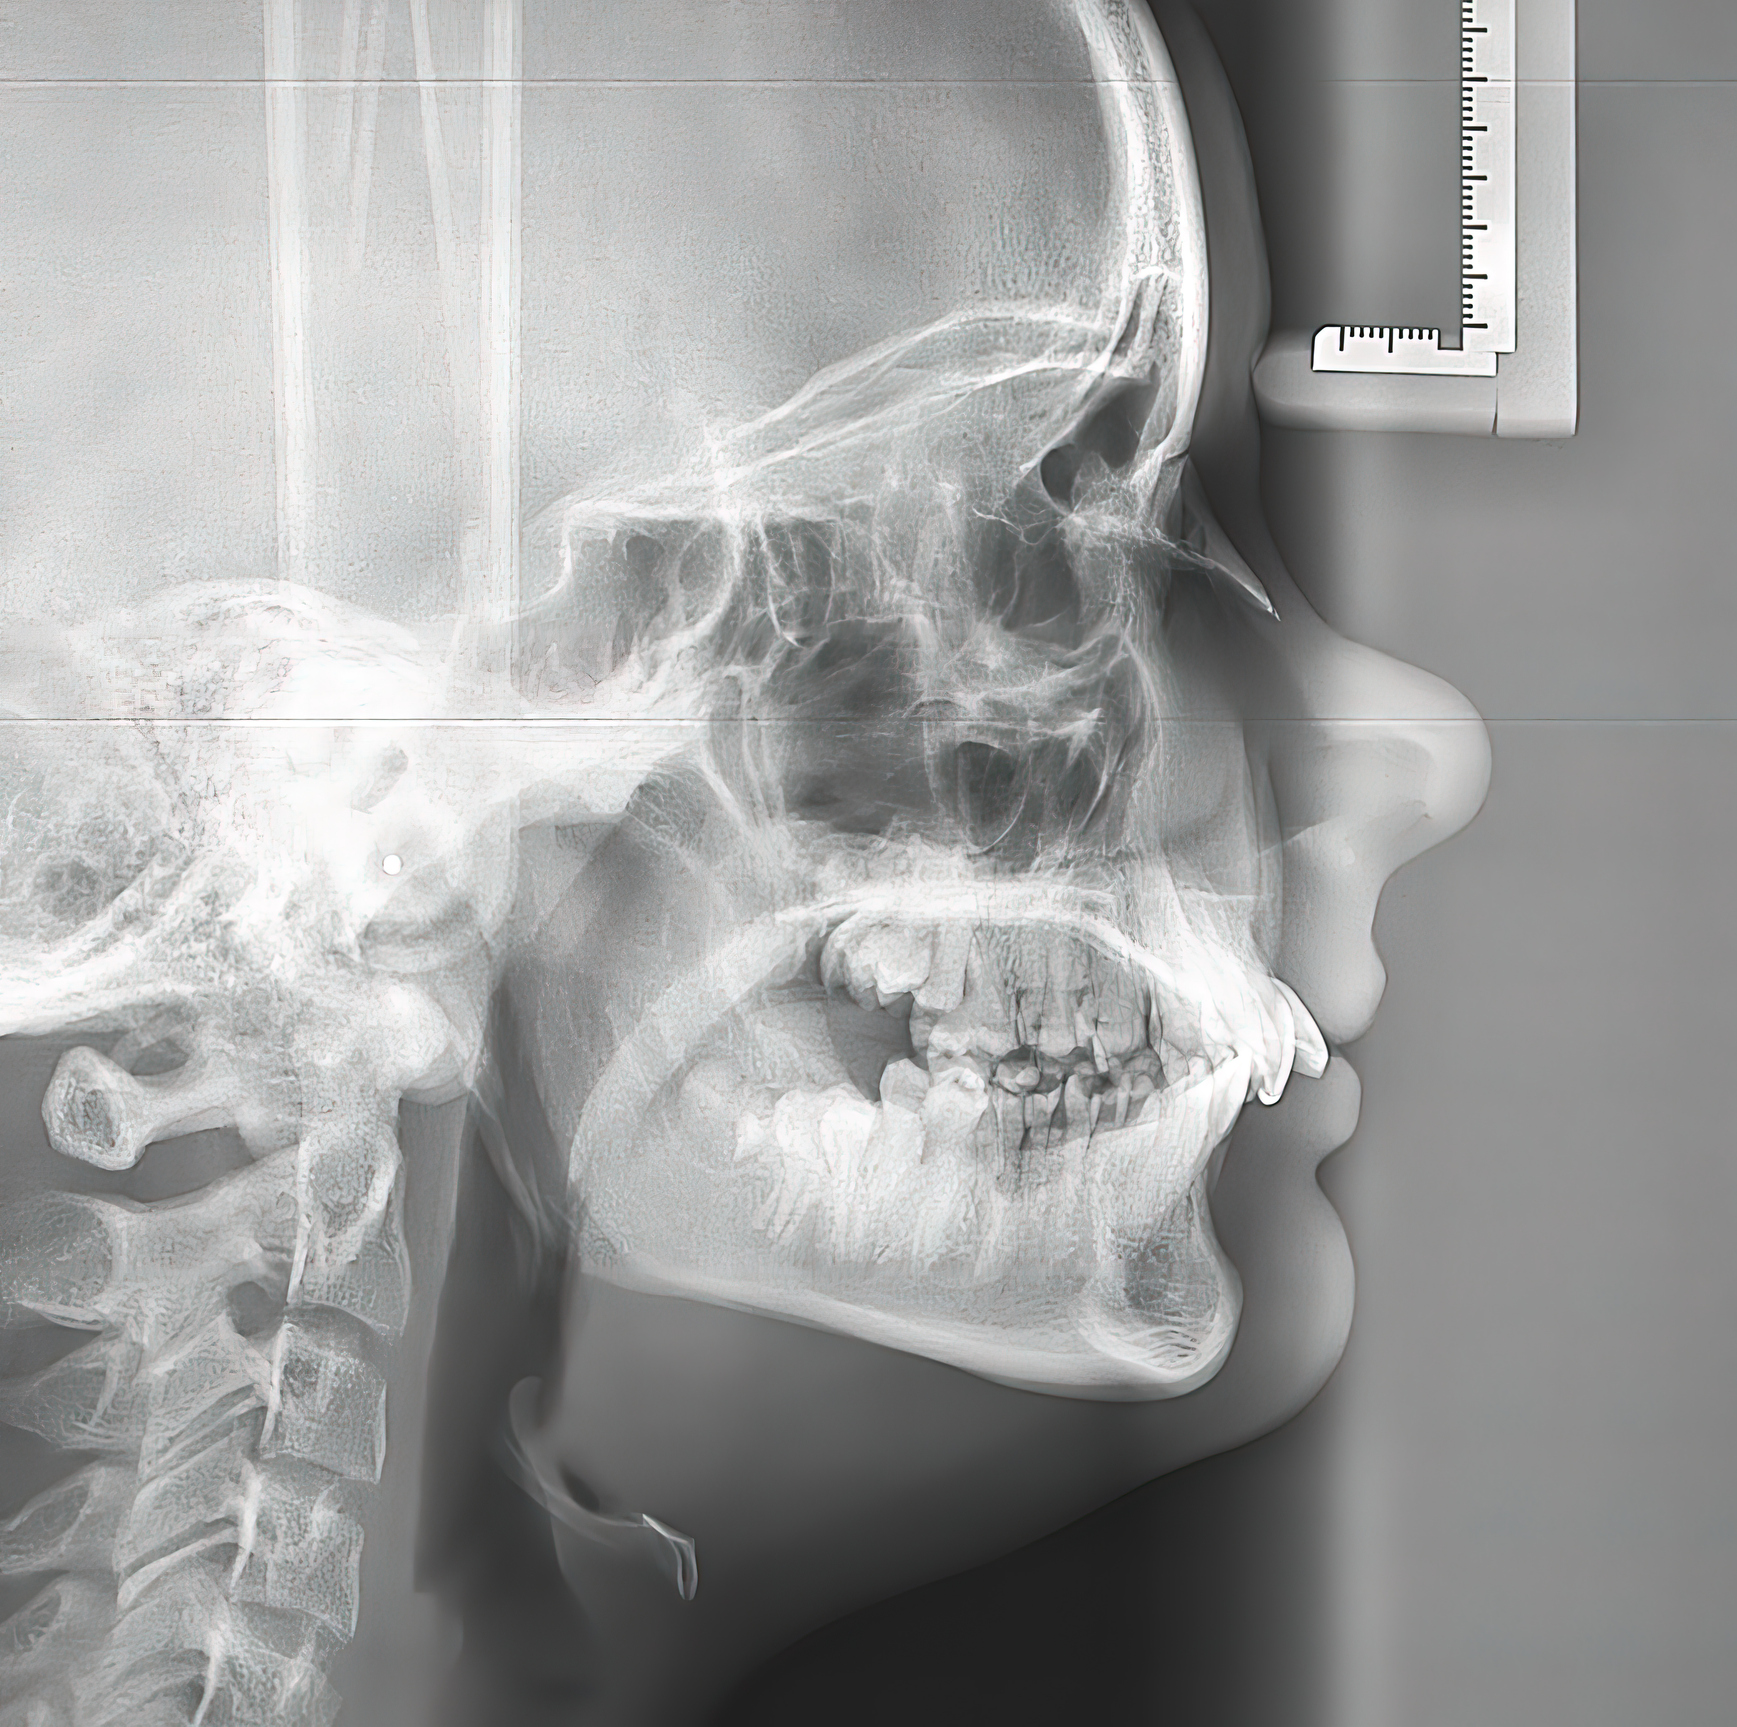

- Cefalométrica o teleradiografía: Se utiliza principalmente en ortodoncia para evaluar el crecimiento de los huesos faciales y la relación entre los dientes y los huesos.

Extraorales: Se toman fuera de la boca y ofrecen una visión más amplia, incluyendo los dientes, maxilares y las articulaciones.

- Tomografía Computarizada Cone Beam (CBCT): Proporciona imágenes tridimensionales de alta resolución, permitiendo una evaluación más detallada de estructuras óseas y tejidos blandos.